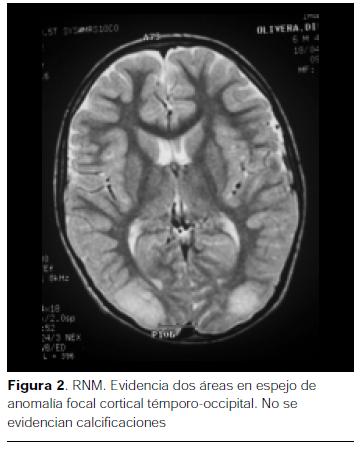

Tomografía axial computada (TAC) de cráneo donde se observan calcificaciones corticales en ambos lóbulos occipitales(figura 1).

En cuanto a las calcificaciones cerebrales, son cortico-subcorticales, serpinginosas, en forma de guirnalda, con doble contorno, topografiándose a nivel parieto-occipital. Típicamente bilaterales y simétricas, electivamente visibles en la TAC de cráneo, tal lo evidenciado en nuestro paciente, no siendo realzadas por medio de contraste intravenoso (1,2,7,8).

Como se observó en nuestro caso, la RNM de cráneo no logra ponerlas en evidencia, solamente muestra la desmielinización periférica a dichas calcificaciones (1,8).

Existen múltiples formas evolutivas, Gobbi y colaboradores (4) describen la forma típica en tres fases. La fase precoz corresponde al debut de la enfermedad con una edad promedio de 6 años, caracterizada por inicio de crisis convulsivas parciales con examen neurológico y desarrollo normales. El EEG muestra sobre un ritmo de base normal en vigilia se presenta descargas de espigas rítmicas, en regiones occipitales. La TAC de cráneo muestra las calcificaciones occipitales bilaterales que obliga a descartar la enfermedad celíaca asintomática. Nuestro paciente se encuentra en ésta etapa evolutiva.